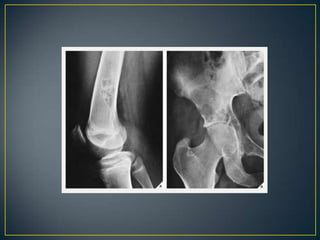

• A multiplicity of malignant lesions usually indicates

metastatic disease, multiple myeloma, or lymphoma.

Very rarely do primary malignant lesions, such as an

osteosarcoma or Ewing sarcoma, present as multifocal

disease. Benign lesions, however, tend to involve

multiple sites, as in polyostotic fibrous dysplasia multiple

osteochondromas, enchondromatosis, Langerhans cell

histiocytosis.